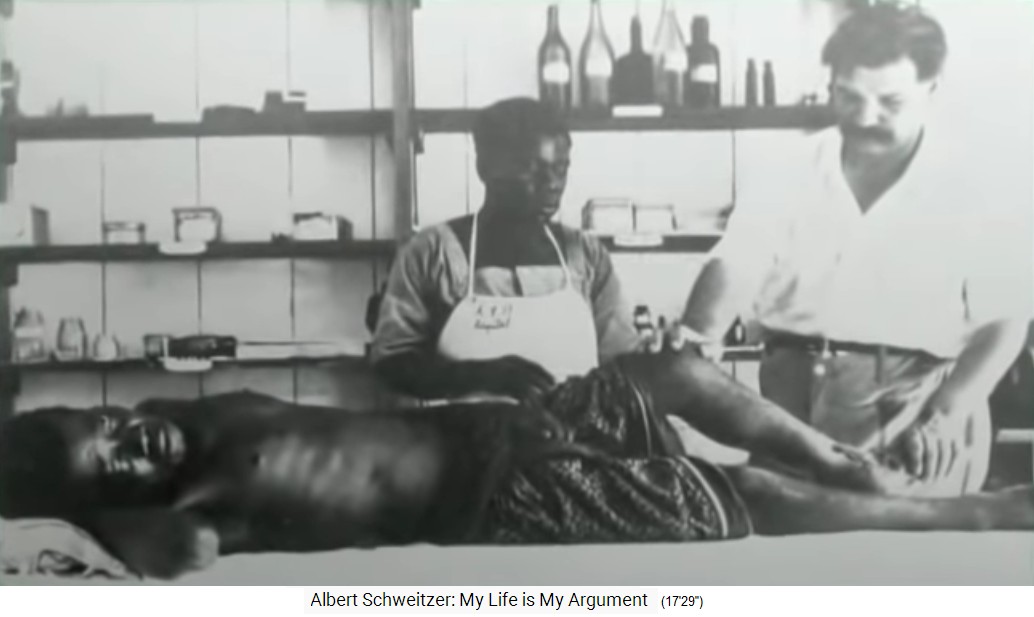

Surgery with Albert Schweitzer

Lambarene, Albert Schweitzer with a patient at the

operating table (it may be assumed the assistant is

Joseph) [14]

Above all, surgery is performed

-- hernias

-- elephantiasis tumors (letters from Lambarene, p.567)

-- broken bones caused by accidents while falling from

trees (letters from Lambarene, p.534)